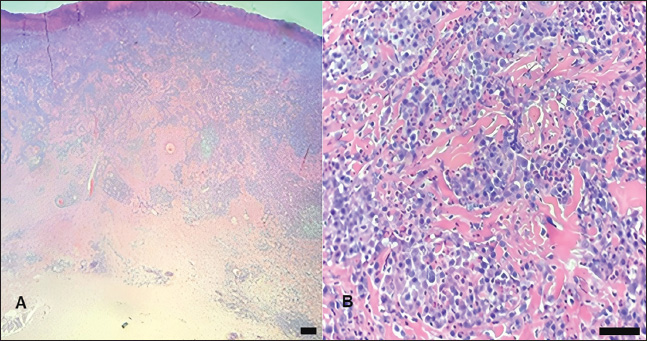

Fig. 5. Hematoxylin and eosin staining of the feline mast cell tumor (Case 3) observed with an optical optic microscope. (A): lesion prior to treatment (D0), characterized by a dense population of mast cells with undifferentiated morphology (10x); (B): Presence of anisokaryosis and pleomorphism of the cancer cells (arrows), characterized by a polygonal to spindle-shaped cell morphology with the presence of central nucleoli (40x); (C): Tissue biopsy showing mast cell tumor after electrochemotherapy, revealing a low cell density (5x); (D): Cells after ECT (Day 45) were characterized by condensed chromatin and eosinophilic cytoplasm (apoptotic cells­—arrows) and more organized collagen fibers, indicating stroma reorganization to a normal pattern (40x). Scale bar 50 µm.

Histopathological examination of the initial (pre-ECT) biopsy revealed cancer cells with intense pleomorphism, showing large polygonal to spindle-shaped cells with marked anisokaryosis, classified as histiocytic high-grade MCT (seven mitotic figures/10 hpf). The analysis of the second biopsy specimen (collected on day 45 after the first ECT course but before the second ECT session) revealed a low density of apoptotic cells characterized by a pyknotic nucleus with condensed chromatin and eosinophilic cytoplasm (Fig. 5). The patient was rechecked every 3 months, and no new lesions or metastasis were observed for 12 months, after which contact was lost.